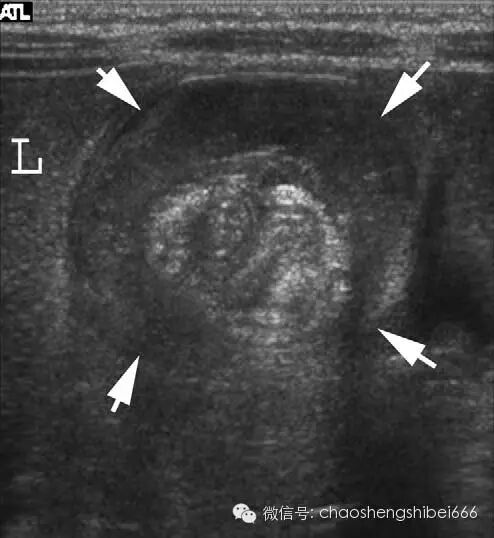

6 4月大男婴肠套叠声像图呈低回声的面包圈征(箭头),中心 可见肠系膜脂肪强回声。L肝脏

7 3岁男孩肠套叠声像图(箭头),套入部肠系膜叠内可见多个发淋巴结(星号)